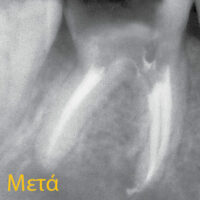

Είναι ο επιστημονικός τομέας της οδοντιατρικής που ασχολείται με το εσωτερικό του δοντιού, δηλαδή κυρίως με τον πολφό (ή νεύρο όπως έχει επικρατήσει εσφαλμένα) και κύριο αντικείμενο είναι η ενδοδοντική θεραπεία (ή απονεύρωση=λανθασμένος όρος). Στο οδοντιατρείο μας παρέχεται προς τους ασθενείς το μεγαλύτερο μέρος της ενδοδοντίας, γίνονται ενδοδοντικές θεραπείες (απονευρώσεις), επαναλήψεις ατελών ενδοδοντικών θεραπειών (απονευρώσεων) και άλλες θεραπευτικές εργασίες που σχετίζονται με τον πολφό.